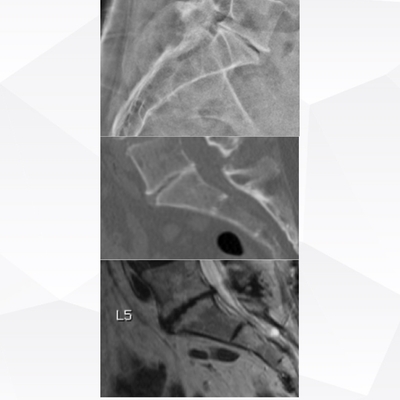

Click on an image below to view more info.